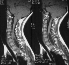

- XRAYS: A 24 degree left thoracic curve from T5 - Tl1

was noted on scoliosis spine films.With the asymmetric abdominal reflexes

and high thoracic left curve she was sent for an MRI scan. This revealed

a large syringomyelia with dilatation in the lower cervical and upper thoracic

area. Also noted was an Arnold-Chiari malformation.